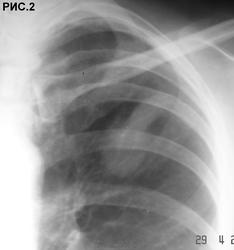

Б-ная 54 г. Живет в небольшом  городе. Поступила в хирургический стационар для холецистэктомии. При ней находился пакет с рентгенограммами органов грудной клетки. Стало известно, что 1 год назад обратилась с бронхолегочными симптомами в поликлинику, где при рентгенографии грудной клетки "выявлено затемнение в легких". После лечения антибиотиками изменения в легких оставались стабильными. Консультирована рентгенологами,онкологами, фтизиатрами, терапевтами, хирургами. Диагноз не установлен. Больная удручена.Хирурги думают. Снимки 6 мес. давности (рис.1,2,3 ).  Рентгенограммы не блеск, но картина везде подобная. Томограмм нет. Ваше слово коллеги! С уважением Nic.

Ответ всегда один - КТ. А без КТ? Не всем дано. В 80% больниц нет КТ. А на боковой я тоже четко не вижу тени. Скорее всего на плевре (передней или задней).

на боковом,похоже,в ретростернальном пространстве находится

наступил, когда был выполнен последний снимок в отделении. Хорошо видно, что имеется частичное опорожнение ретенционной бронхиальной кисты (рис.4, рис.5). Со слов больной,  незадолго до поступления в стационар имело место отхождение мокроты светлокоричневого цвета без запаха. При анализе выписок из различных учреждений процесс в легких рассматривался как туберкулема легких, туберкулема легких или опухоль, опухоль легкого, патология сосудов легкого, диагноз неясен (овальный фокус затемнения в легком). С уважением Nikolas